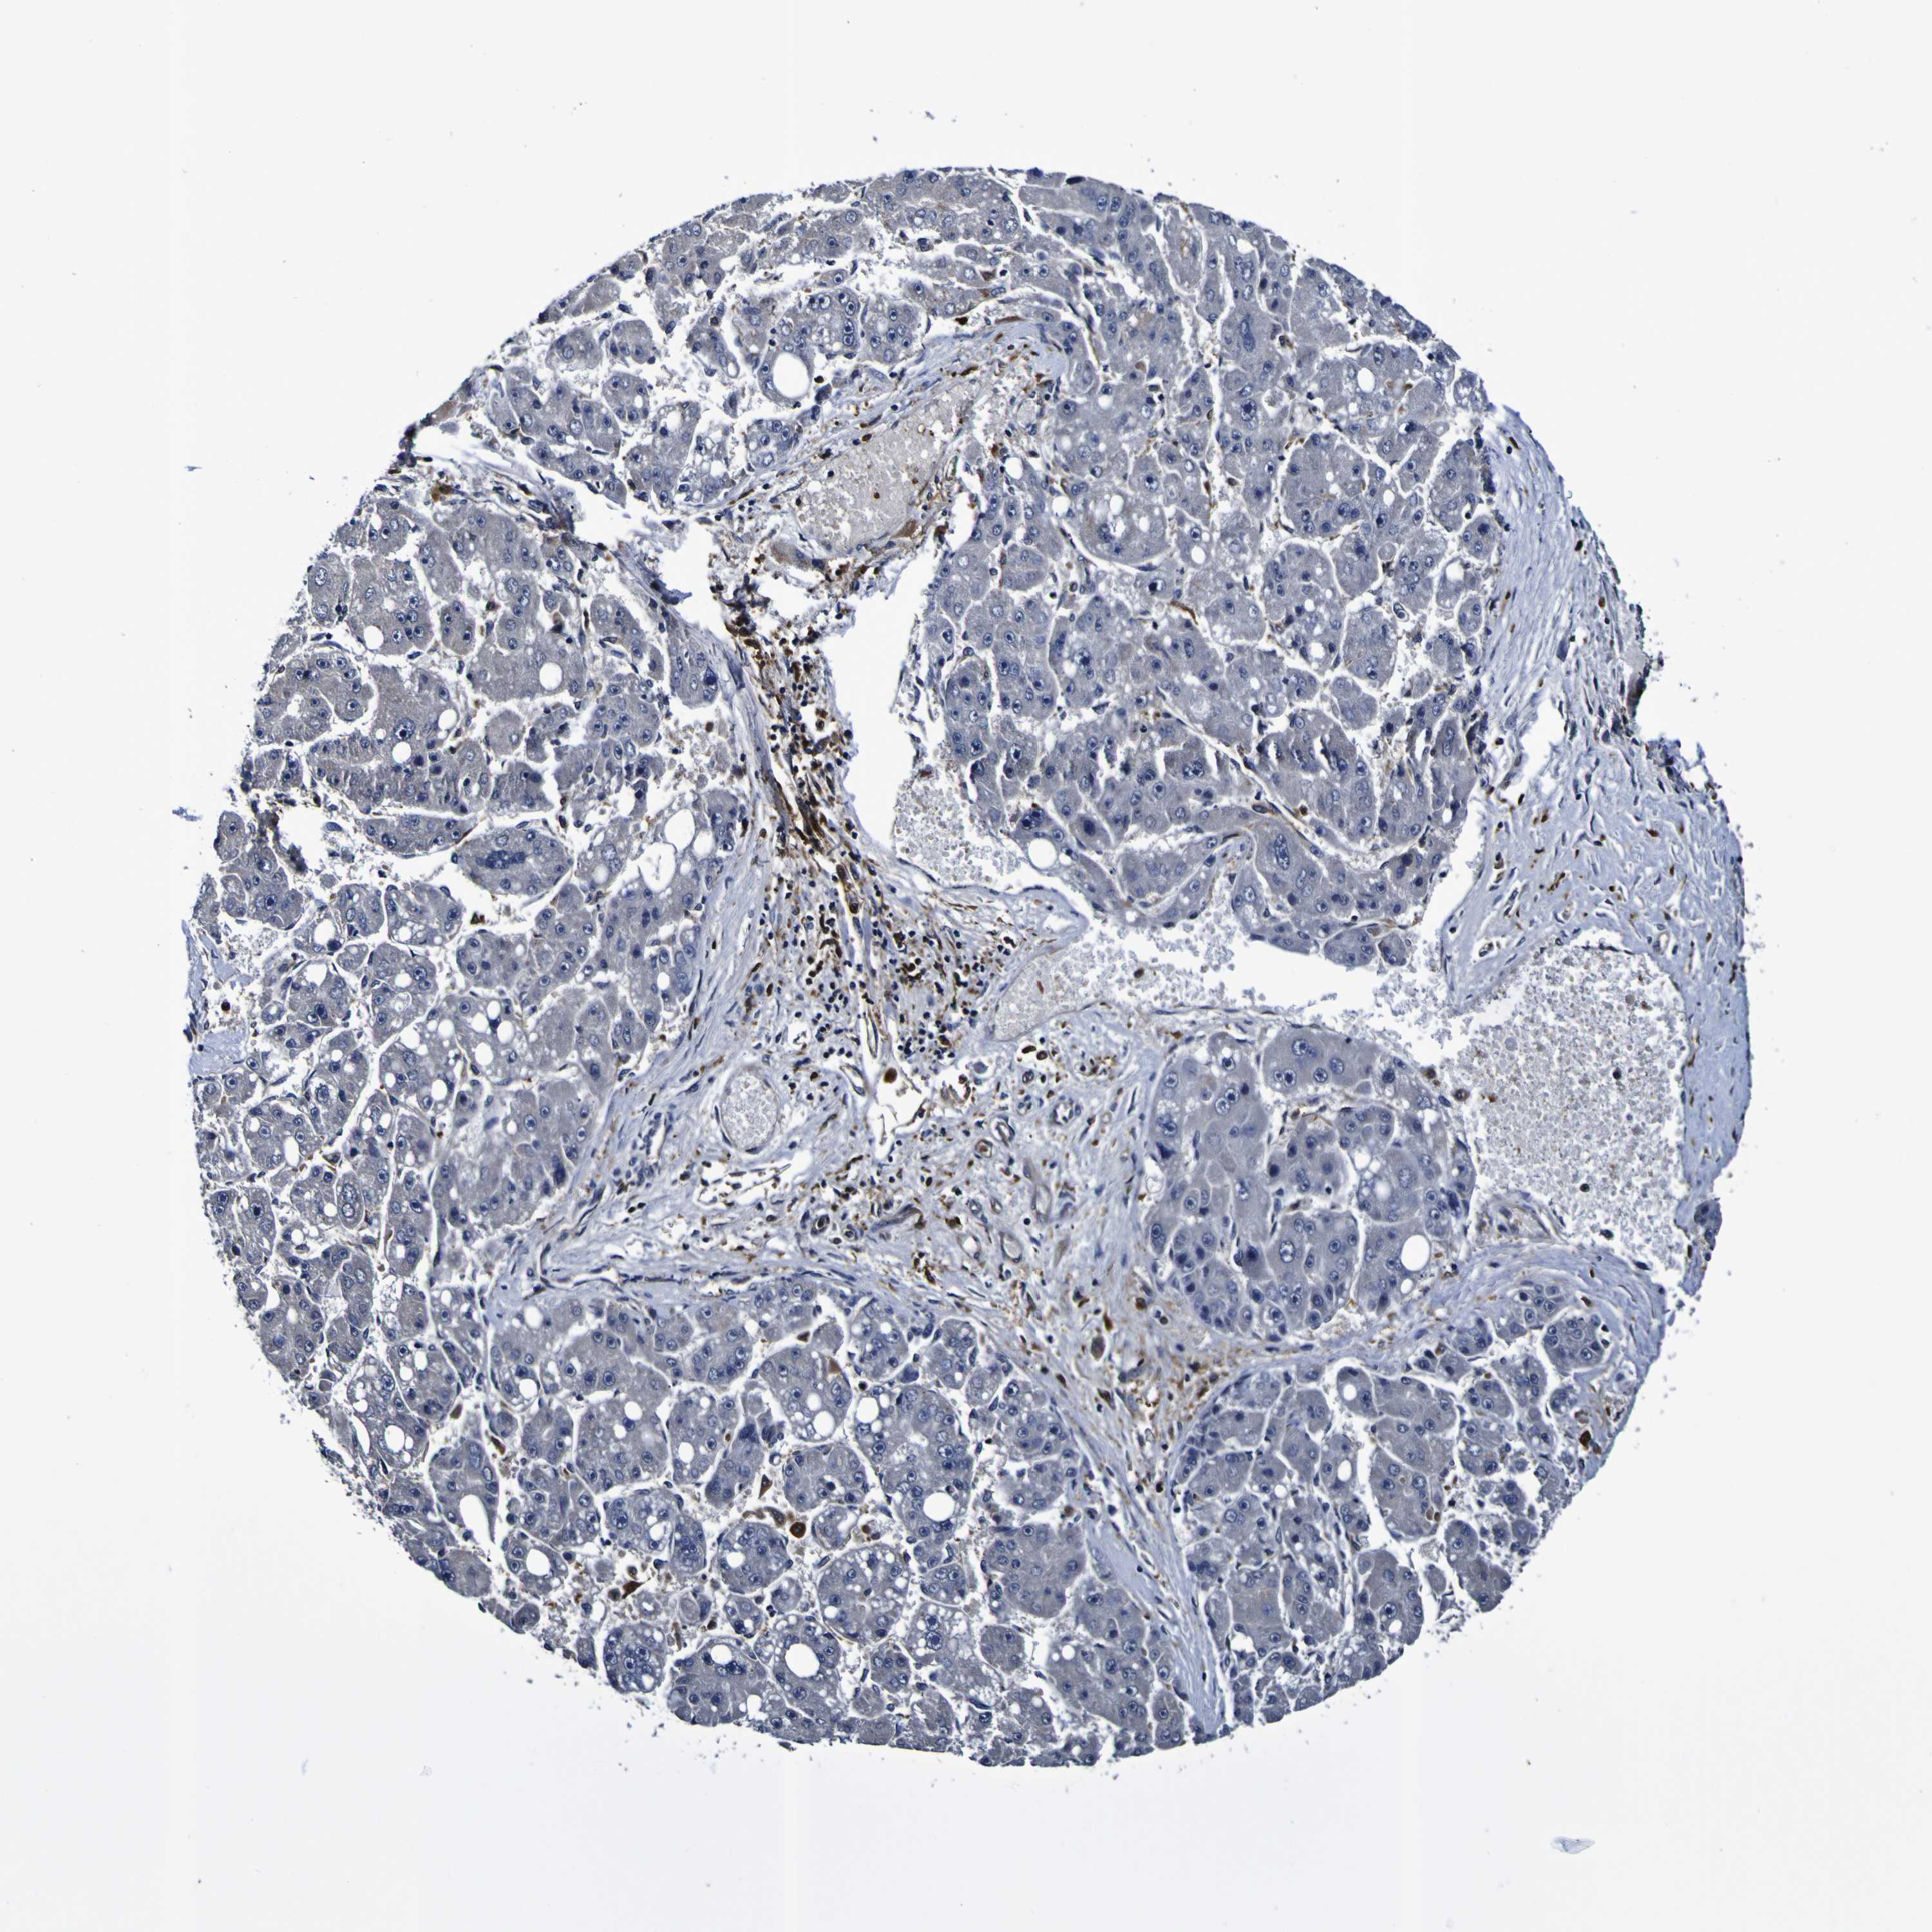

LIVER CANCER - Protein expressioni

A mouse-over function shows sample information and annotation data. Click on an image to view it in a full screen mode. Samples can be filtered based on level of antibody staining by selecting one or several of the following categories: high, medium, low and not detected. The assay and annotation is described here.

Note that samples used for immunohistochemistry by the Human Protein Atlas do not correspond to samples in the TCGA dataset.

Antibody stainingi

Antibody staining in the annotated cell types in the current human tissue is reported as not detected, low, medium, or high, based on conventional immunohistochemistry profiling in selected tissues. This score is based on the combination of the staining intensity and fraction of stained cells.

Each image is clickable and will lead to virtual microscopy that enables deeper exploration of all samples and also displays staining intensity scores, fraction scores and subcellular localization as well as patient and tissue information for each sample.

Antibody HPA044758

Antibody CAB011582

Staining

High

Medium

Low

Not detected

Intensity

Strong

Moderate

Weak

Negative

Quantity

>75%

75%-25%

<25%

None

Location

Nuclear

Cytoplasmic/membranous

Cytoplasmic/membranous,nuclear

Cholangiocarcinoma

Carcinoma, Hepatocellular, NOS